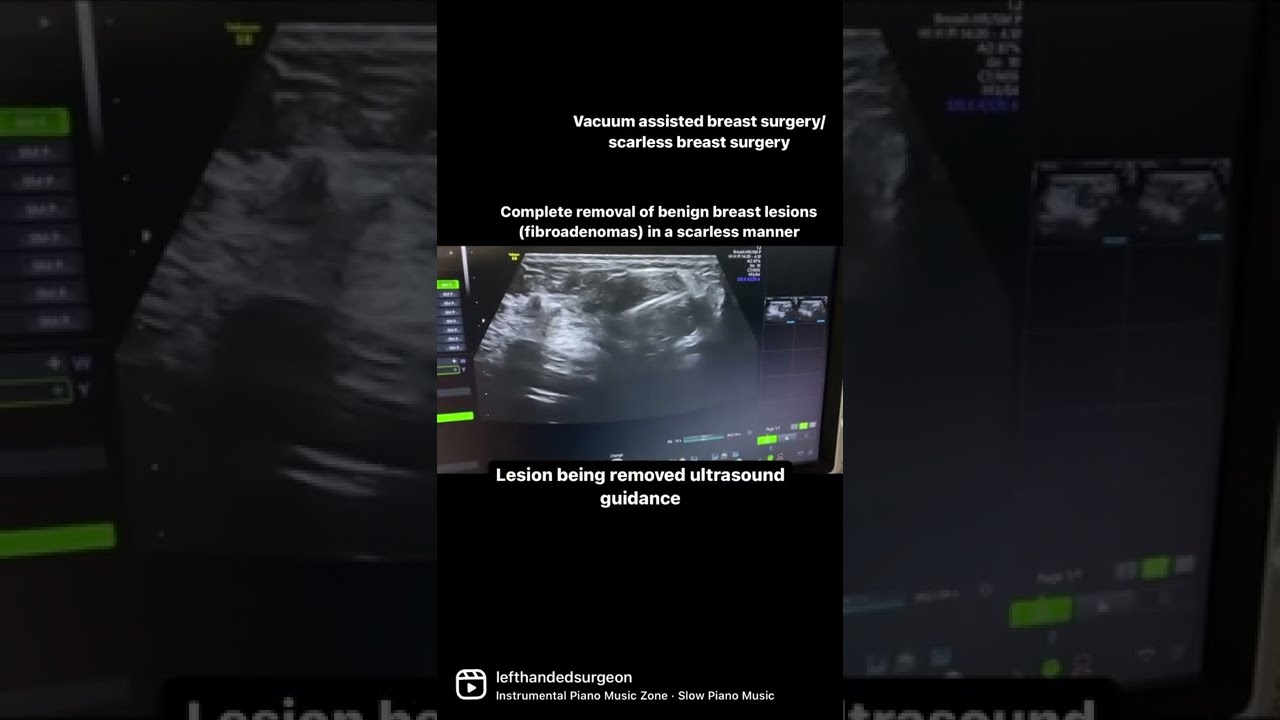

Identifying whether a lump is benign typically involves several steps:

Physical Examination: A healthcare provider will perform a thorough examination. Imaging Tests: Ultrasound or mammograms may be utilized for further evaluation. Biopsy: In certain cases, a sample may be taken for laboratory analysis.The Importance of Regular Screening